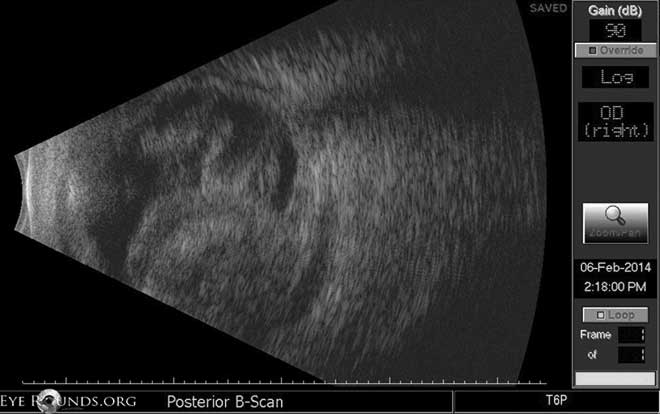

Right eye: dense large appositional hemorrhagic choroidals; no retinal detachment; no liquefaction or layering of blood clot.